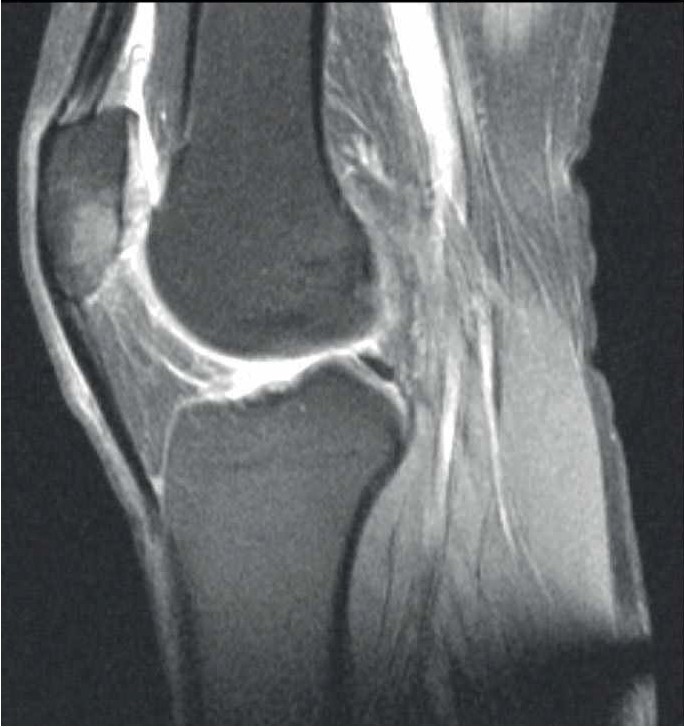

- Мужчина В., 36 лет, без отягощенного соматического и семейного анамнеза в августе 2021 г. перенес тяжелую форму COVID-19. Находился на стационарном лечении 17 дней. Пациенту назначали антикоагулянты (эноксапарин натрия 1,6 мл/сут на весь период лечения), противовирусный препарат фавипиравир (3600 мг – 1 сут, затем 1600 мг – 6 сут). В стационаре терапия дексаметазоном продолжена в дозировке 20 мг ежедневно с последующим снижением до 4 мг к моменту выписки – 272 мг (в пересчете на преднизолон – 1813 мг). После выписки из стационара принимал ривароксабан 15 мг/сут.

В декабре 2021 г. стала беспокоить боль распирающего характера в обоих тазобедренных суставах в покое, интенсивность боли снижалась при нагрузке, и в поясничном отделе позвоночника (6 баллов по ВАШ). Обратился к неврологу, и было начато консервативное лечение люмбалгии. В феврале 2022 г. вследствие неэффективности консервативного лечения и сохранения болевого синдром выполнена СКТ таза. Обнаружены двусторонний коксартроз, асептический некроз головок бедренных костей (рис. 3).

Рис. 3. СКТ таза у пациента В. Диагноз – двусторонний коксартроз, асептический некроз головок бедренных костей.

В связи с наличием субхондрального перелома головки правой бедренной кости пациенту выполнено тотальное эндопротезирование правого тазобедренного сустава.

В позднем послеоперационном периоде пациент отмечал восстановление функции правой нижней конечности, отсутствие болевого синдрома (0 баллов по ВАШ) в правом тазобедренном суставе